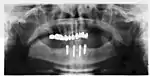

The long-term success of implants is determined in part by the forces they have to support. As implants have no periodontal ligament, there is no sensation of pressure when biting so the forces created are higher. To offset this, the location of implants must distribute forces evenly across the prosthetics they support.[28]: 15–39 Concentrated forces can result in fracture of the bridgework, implant components, or loss of bone adjacent the implant.[29] The ultimate location of implants is based on both biologic (bone type, vital structures, health) and mechanical factors. Implants placed in thicker, stronger bone like that found in the front part of the bottom jaw have lower failure rates than implants placed in lower density bone, such as the back part of the upper jaw. People who grind their teeth also increase the force on implants and increase the likelihood of failures.[15]: 201–208